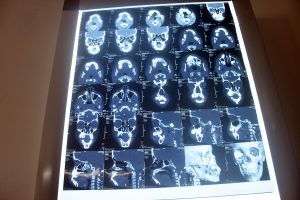

Derrick på 13 år havde levet med en smertefuld hævelse i sin højre kæbe i flere måneder. Det var blevet stadig sværere at spise og tale, og ubehaget var konstant. En scanning arrangeret af HD afslørede årsagen - et osteom (en godartet knogletumor) sammen med en dermoid cyste i hans submandibulære kirtel, som ligger lige under kæben.

På grund af de alvorlige smerter trådte vi til for at finansiere Derricks operation. Indgrebet blev udført af kæbekirurgen Dr. Macho, som har hjulpet mange børn med komplekse kæbesygdomme. Under operationen blev både osteomet og den dermoide cyste fjernet med succes - hvilket lindrede Derricks smerter og forhindrede yderligere skader på hans kæbe og det omgivende væv.

Donationerne dækkede alle dele af hans behandling, herunder diagnostiske scanninger, anæstesi, kirurgisk udstyr, medicin og postoperative opfølgningsaftaler.